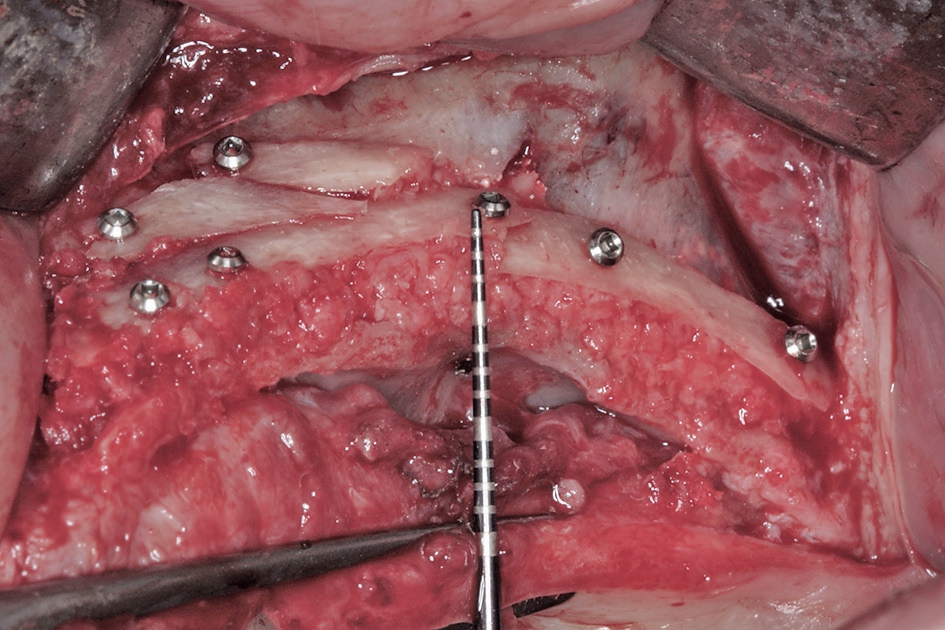

Der chirurgische Behandlungsteil bestand aus drei Eingriffen im Abstand von jeweils etwa drei Monaten. Im ersten Eingriff wurden die augmentativen Maßnahmen im atrophierten Oberkiefer (Abb. 4) nach retromolarer Knochenentnahme aus dem rechten Unterkiefer (Abb. 5 bis 7) in horizontaler und vertikaler Dimension vorgenommen. Dazu wurde der Kiefer durch das Anbringen von autologen Knochenblöcken nach dem biologischen Konzept lateral verbreitert. Mittels der Schalentechnik werden dabei die Blöcke auf Distanz gesetzt und der Zwischenraum mit autologen Knochenpartikeln gefüllt (Abb. 8 und 10). Durch die Partikulierung des Knochens wird die Oberfläche vergrößert und es kann eine bessere Revaskularisierung des augmentierten Bereichs erfolgen [5].

Zudem war beidseitig eine Sinusbodenelevation notwendig (Abb. 9), die mittels lateralen Zugangs durchgeführt wurde. Eine entstandene Perforation wurde vernäht und mit einer Kollagenmembran abgedeckt (Abb. 11). In der sogenannten Schichttechnik werden bei der Sinuselevation im kaudalen Bereich autologe Knochenpartikel eingebracht, so dass die Implantate später etwa 10 mm im Eigenknochen stehen. Im kranialen Bereich wird langsam resorbierendes Knochenersatzmaterial (Symbios®, DENTSPLY Sirona, Mannheim) eingebracht. Diese dünne Schicht Biomaterial schützt vor Resorptionen durch den Druck in der Kieferhöhle. Auch auf der linken Seite des Oberkiefers wurde der Kieferkamm lateral augmentiert (Abb. 12 und 13). Das Konzept der Schichttechnik beim Sinuslift dient der Verkürzung der Behandlungszeit, so dass die Implantate schon nach einem früheren Zeitpunkt inseriert werden können. Die Insertion der Implantate ist nach dem hier vorgestellten Konzept bereits nach drei bis vier Monaten möglich im Vergleich zu 7 bis 8,5 Monaten beim Einsatz von reinem Biomaterial und gleichzeitiger geringer Restknochenhöhe [13]. Die Abdeckung des Sinusfensters erfolgte mit einer nicht resorbierbaren Membran aus Reintitan (FRIOS® BoneShield, DENTSPLY Implants, Mannheim) bevor der Verschluss des augmentierten Bereiches durch den Mukoperiostlappen erfolgt.

Vor dem zweiten OP-Eingriff nach 4 Monaten wurde im Labor eine Bohrschablone angefertigt. Zudem wurde ein DVT angefertigt, um im Sinne eines Backward planning die ideale Implantatposition planen zu können. Bei Eröffnung des augmentierten Kieferbereiches zeigte sich im augmentierten Bereich eine gute Regeneration und Revaskularisierung des Knochens (Abb. 14 bis 17). Sechs Implantate konnten somit in den augmentierten Bereich (Astratech EV®, DENTSPLY Sirona, Mannheim) mit ausreichender Länge und Durchmesser in Form einer gleichmäßigen Pfeilerverteilung in den Kieferknochen Inseriert werden (Abb. 18).